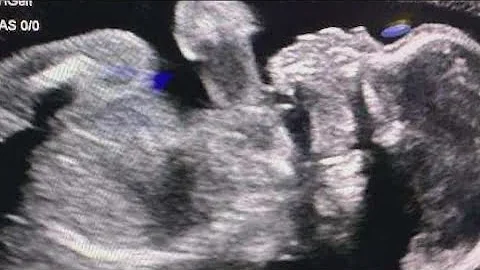

The infant, baby Chance, born to a metro Atlanta woman who was kept on life support for months after being declared brain dead ...